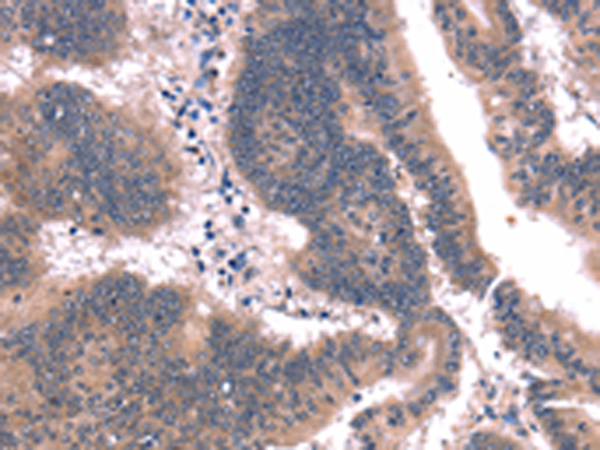

分类: 科研抗体货号: P04873别名: C4orf7; FDC-SP应用: IHC反应种属: Human